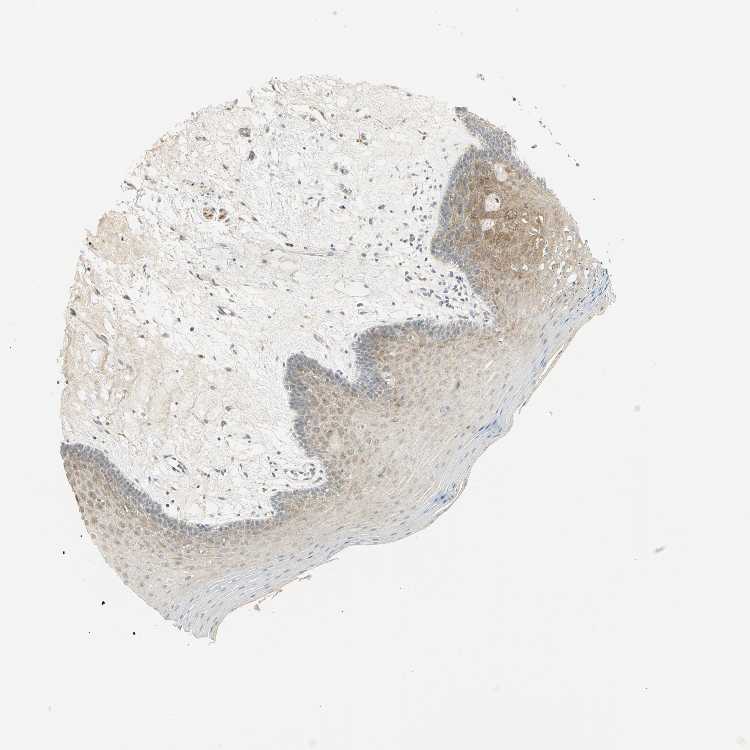

TISSUE PRIMARY DATA ORAL MUCOSA Show tissue menu

ORAL MUCOSA - Antibody stainingi

Antibody staining in the annotated cell types in the current human tissue is reported as not detected, low, medium, or high, based on conventional immunohistochemistry profiling in selected tissues. This score is based on the combination of the staining intensity and fraction of stained cells.

Each image is clickable and will lead to virtual microscopy that enables deeper exploration of all samples and also displays staining intensity scores, fraction scores and subcellular localization as well as patient and tissue information for each sample.

Antibody HPA041785Antibody HPA069311Antibody CAB005580

Squamous epithelial cells LowMediumLow